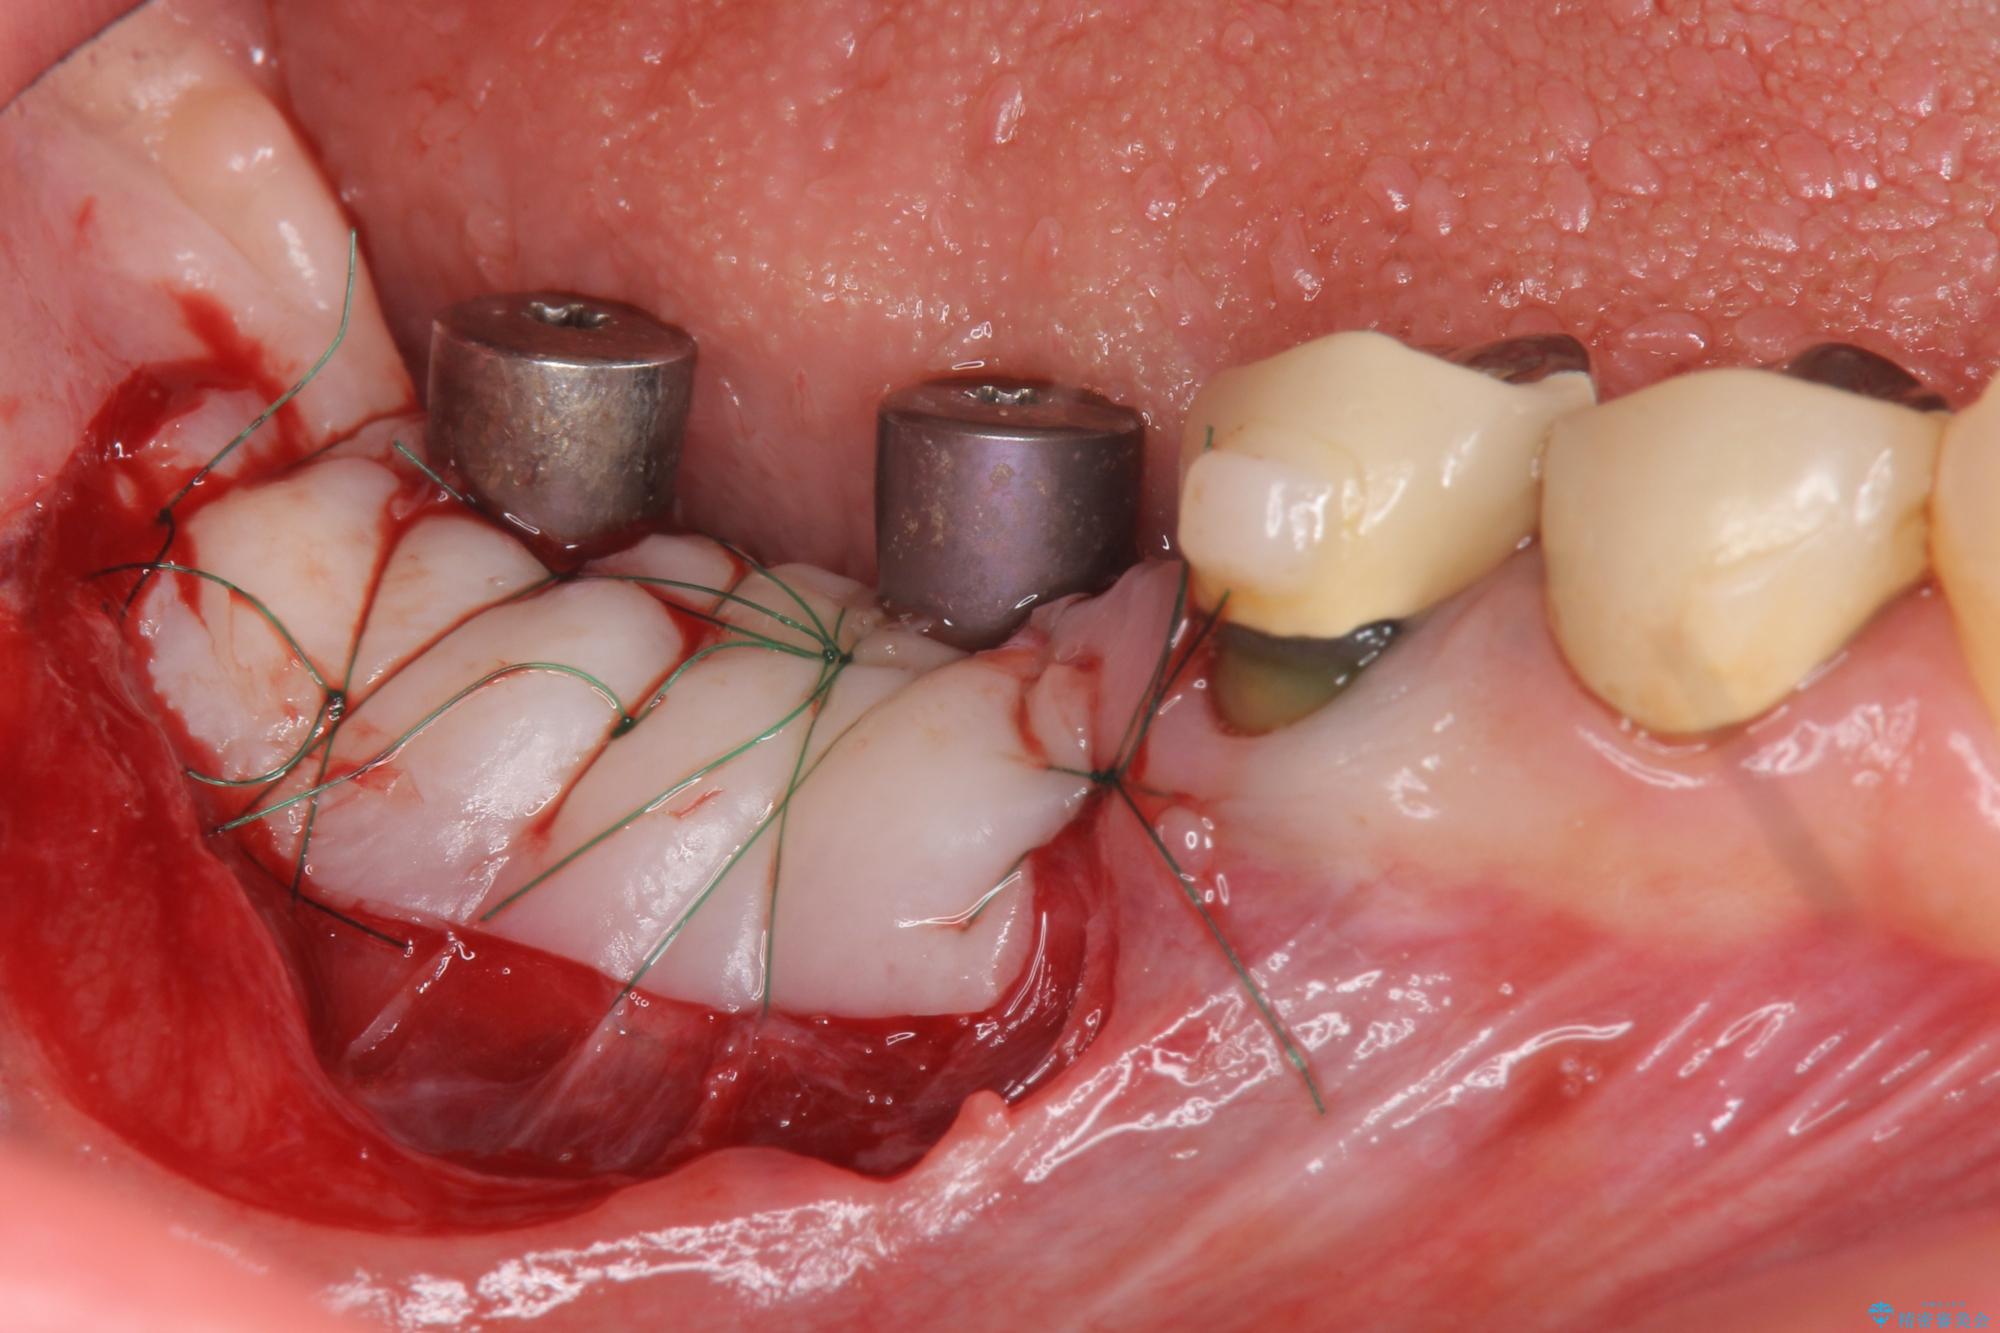

虫歯に伴い歯槽骨の吸収も見られたので造骨後、インプラントを用いて咬合機能を回復します。

また、機能後のインプラント周囲の清掃性を高めるため遊離歯肉移植術を行っています。

治療中

遊離歯肉移植術を伴うインプラント治療 治療中画像 遊離歯肉移植術を伴うインプラント治療 治療中画像 遊離歯肉移植術を伴うインプラント治療 治療中画像 遊離歯肉移植術を伴うインプラント治療 治療中画像 遊離歯肉移植術を伴うインプラント治療 治療中画像 遊離歯肉移植術を伴うインプラント治療 治療中画像